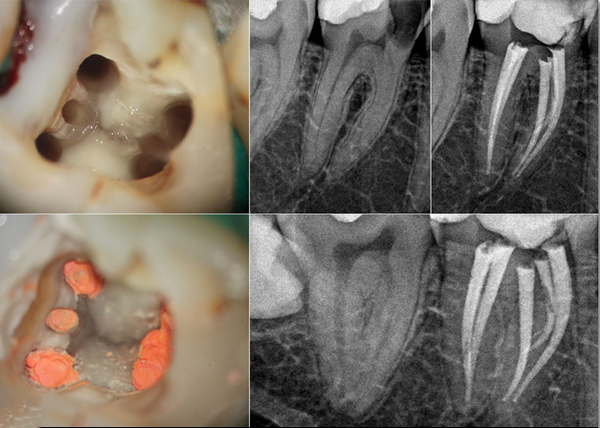

无论是昼夜温差的影响、体位变化的压力还是心理因素的交织,归根结底,牙齿晚上疼痛白天不疼且伴随松动的现象往往与牙齿或牙周组织的病变密切相关。及时寻求专业牙医的诊治是解决问题的关键。通过详细的口腔检查,牙医可以有效判断牙齿松动的原因,如牙周病、根尖周炎等,并制定相应的治疗方案,如洁牙、根管治疗、牙周手术或牙齿固定等,以恢复牙齿的健康与稳固。